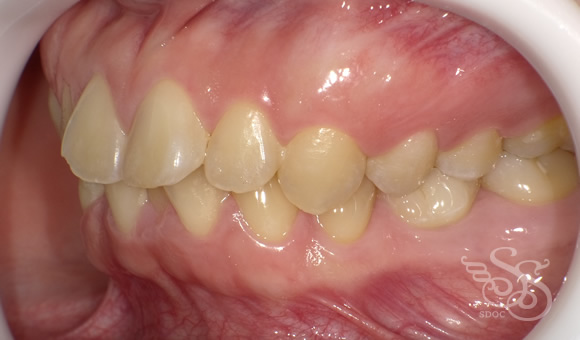

右側:術前

Bi-max症例ですね。

あと、この患者さまは

下顎5番の 先欠でEが残存していました。

動的治療期間 2年4ヶ月でした。

歯ならびだけでなく

口もとの前突感もなくなり

素敵な口もとになりました。